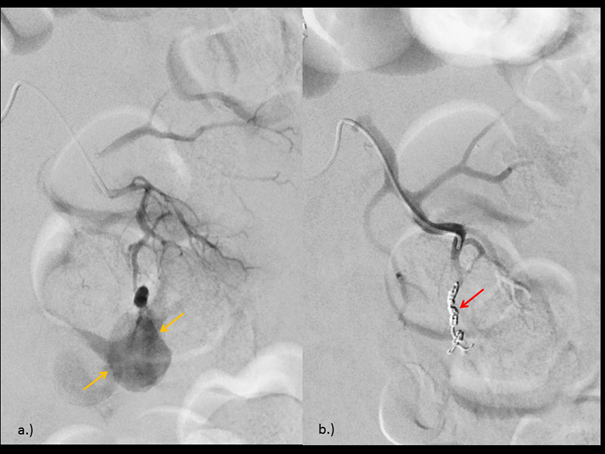

The patient underwent endovascular selective embolization with coil. The digital subtraction angiography (DSA) confirmed the presence of an arterial branch supplying the pseudoaneurysm in the lower pole of the left kidney, followed by coil placement. (Figure 4)

Figure 4 (a) Digital subtraction angiography (DSA) showing the presence of an arterial branch supplying the RAP (yellow arrow) in the lower pole of the left kidney. (b) DSA after coiling procedure (red arrow).